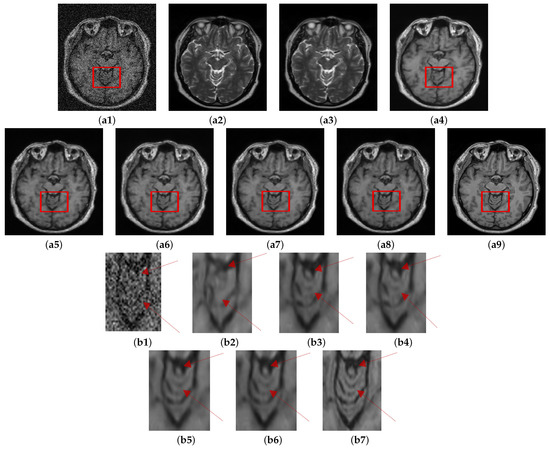

Another experiment (Experiment II) was conducted on the HH dataset using 13% noise. The denoising results are shown in Figure 8 along with enlarged regions for careful inspection. Table 6 shows the quantitative assessment results on different variants of data (i.e., registered and unregistered) using two different loss functions. Among the variants of the proposed method, it is observed that registration between the corresponding T1 and T2 images together with employing SSIM as loss function with MSE facilitates in improving the structural similarity between denoised image and ground truth as implied by the higher SSIM values in the case of C M G D N e t s g compared to its corresponding variants C M G D N e t r s and C M G D N e t s s ; however, noticeable improvement in PSNR values was not observed under this configuration.

Figure 8. Role of using cross-modal guidance information in denoising: Results of C M G D N e t method (a1) Noisy. (a2) Unreg. T2. (a3) Reg. T2. (a4) T1-T1. (a5) C M G D N e t r s . (a6) C M G D N e t s s . (a7) C M G D N e t r g . (a8) C M G D N e t s g . (a9) GT, Corresponding enlarged ROI (b1) Noisy. (b2) T1-T1. (b3) C M G D N e t r s . (b4) C M G D N e t s s . (b5) C M G D N e t r g . (b6) C M G D N e t s g . (b7) GT.